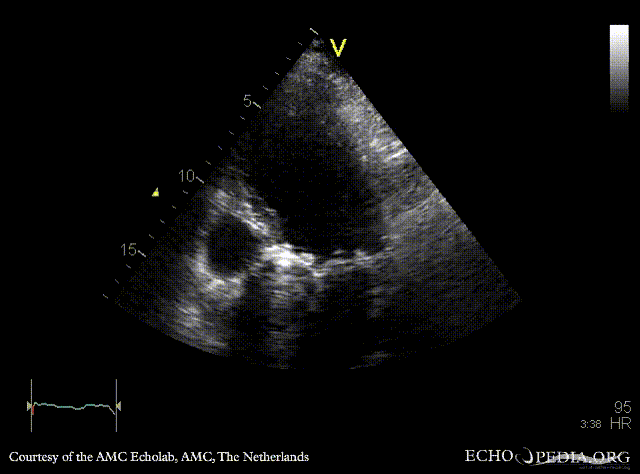

Continuous-wave signal of severe aortic regurgitation